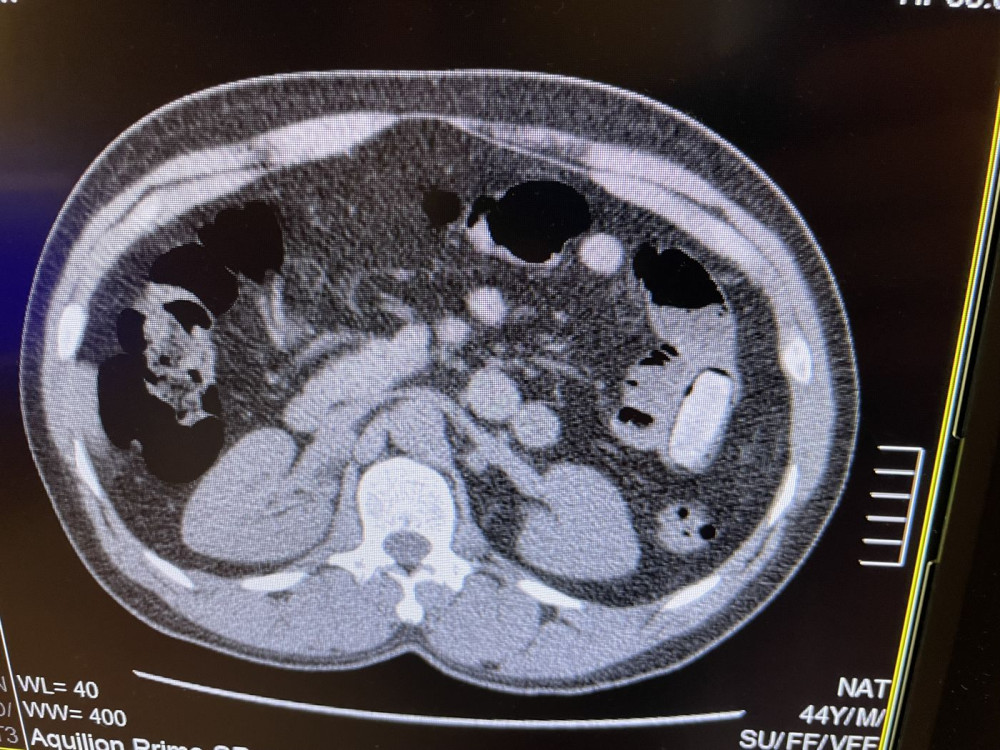

Nigérijský pašerák drog spolykal 55 kapslí s kokainem. Odhalil ho v linkovém autobusu speciálně vycvičený pes